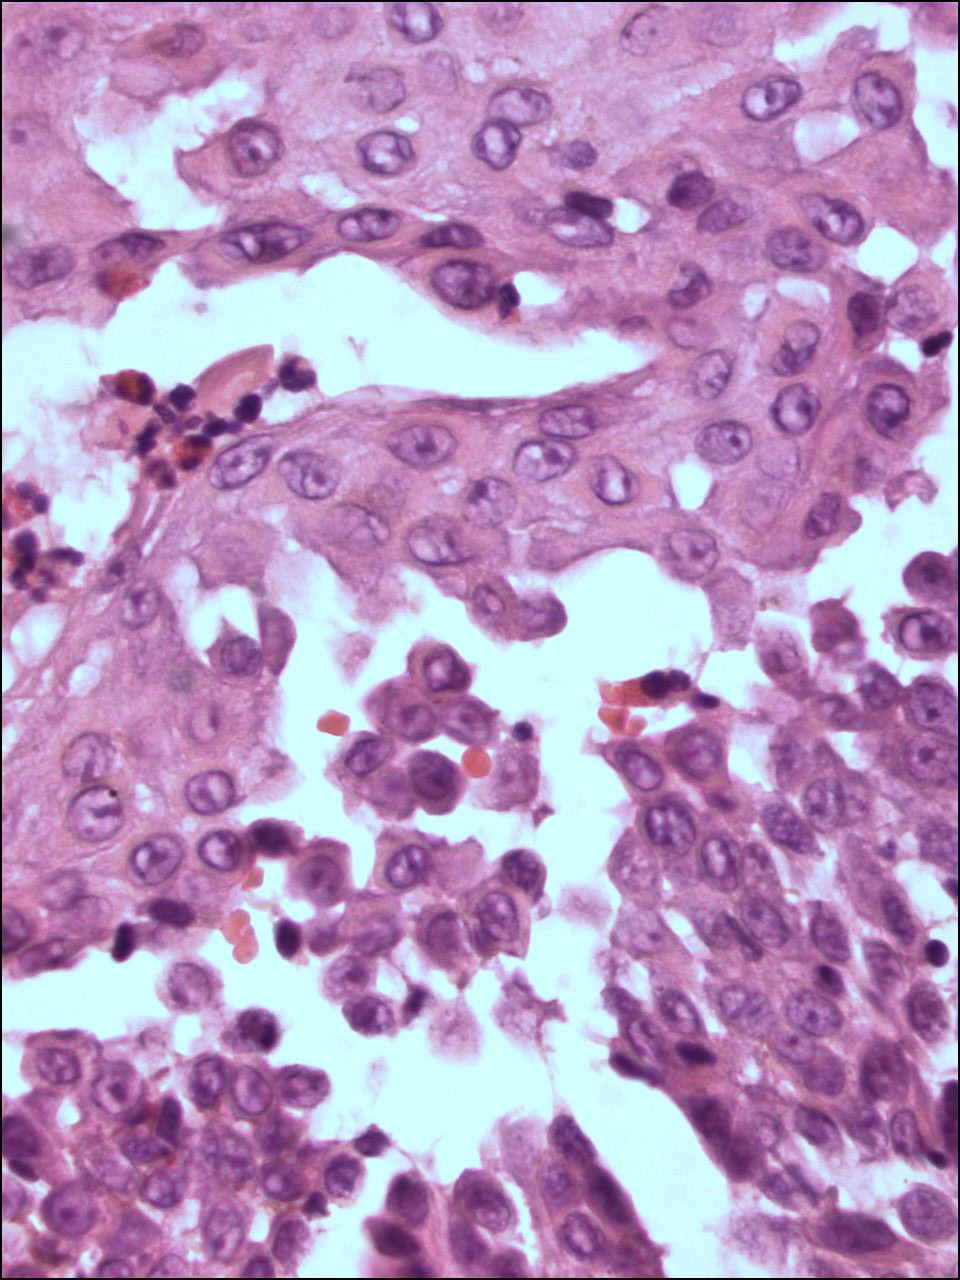

PA:Histologisch

is er sprake van een intra-epidermale splijting (

acantholyse) op suprabasaal

niveau. De keratinocyten liggen op sommige plaatsen volledig los van elkaar

hetgeen de indruk maakt van een bouwvallige ingestorte muur ('dilapidated brick

wall'). Het histologisch beeld is moeilijk te onderscheiden van gewone pemphigus,

maar wel met immunofluorescentie (negatief bij Hailey-Hailey). Bij beide

ziekten is de blaar het gevolg van acantholyse. Verschillen zijn

dat de acantholyse bij Hailey Hailey uitgebreider is en over de hele epidermisdikte voorkomt, en

dat de

dyskeratose minder is

dan bij pemphigus.

| PA pemphigus

benigna |

PA pemphigus